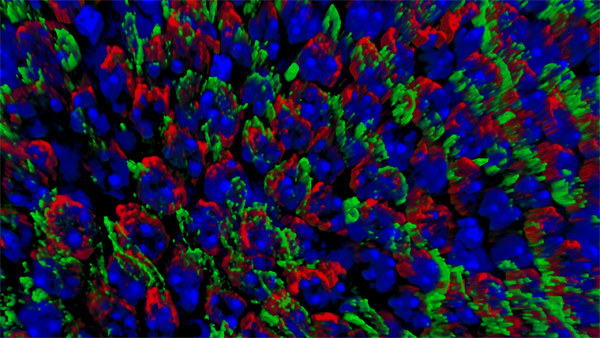

We recently proposed that cones suffer from a nutrient shortage induced by the disruption of the retinal architecture once most rods have been lost (Punzo et al., 2009). Because rods outnumber cones at a ratio of >20:1 and photoreceptors account for approximately 75% of all retinal cells, loss of rods severely alters the retinal architecture. Thus we hypothesized that once rod death progresses beyond a critical threshold, cone death initiates as a cell autonomous event due to a reduction in nutrient flow from the adjacent cell layer, the retinal-pigmented epithelium. This hypothesis was based on the following findings: First, cone death always initiates only after approximately 90% of rods have died irrespective of the rod death kinetics. Second, during the period of cone degeneration cones display signs of prolonged starvation. Finally, during cone death, we observed gene expression changes in many metabolic genes and genes of the insulin/mammalian target of rapamycin (mTOR) pathway, a key pathway controlling cell metabolism. To test if activation of the insulin/mTOR pathway alters cone survival, we treated the fast progressing rd1 mouse model of Retinitis Pigmentosa with daily systemic injections of insulin. While cone survival did improve, the therapeutic effect of insulin lasted only for a period of four weeks possibly due to the negative feedback loop within the insulin/mTOR pathway.

To evaluate the long-term therapeutic potential of the insulin/mTOR pathway on cone survival, and test if insulin acted directly on cones through this pathway, we have now constitutively activated this pathway in cones through use of mouse genetics in two mouse models of Retinitis Pigmentosa. This has led to a robust and unprecedented cone survival effect in two mouse models of Retinitis Pigmentosa and to the finding that cone survival is driven solely by increased mTOR complex 1 activity (rollover image; Venkatesh et al., 2015). To study why the initial robust survival effect of constitutively activated mTORC1 does not persist indefinitely we further study the consequences of altered mTORC1 activity (Venkatesh et. al., 2016). Our studies show that it is not the strength of survival is directly dependent of the strength of mTORC1 activation but that the duration of the effect depends on the system's ability to intermittently turn of mTORC1. This knowledge will allow us to identify downstream genes of mTORC1 that mimic the positive effect of increased mTORC1 activity, without altering the systems ability to intermittently turn of mTORC1. In summary, the knowledge gained from these two studies will allow us to identify downstream target genes or pathways that when manipulated should extend vision in affected individual (see Jean Bennett commenting). For example, rAAV mediated gene transfer of mTORC1 targets in cones may provide a feasible approach for future treatments in humans. Alternatively, drugs that increase mTORC1 activity could be delivered to the retina through slow releasing eye implants. The focus of our current research is to identify the correct mTORC1 targets that can be used to prolong vision in humans with Retinitis Pigmentosa.